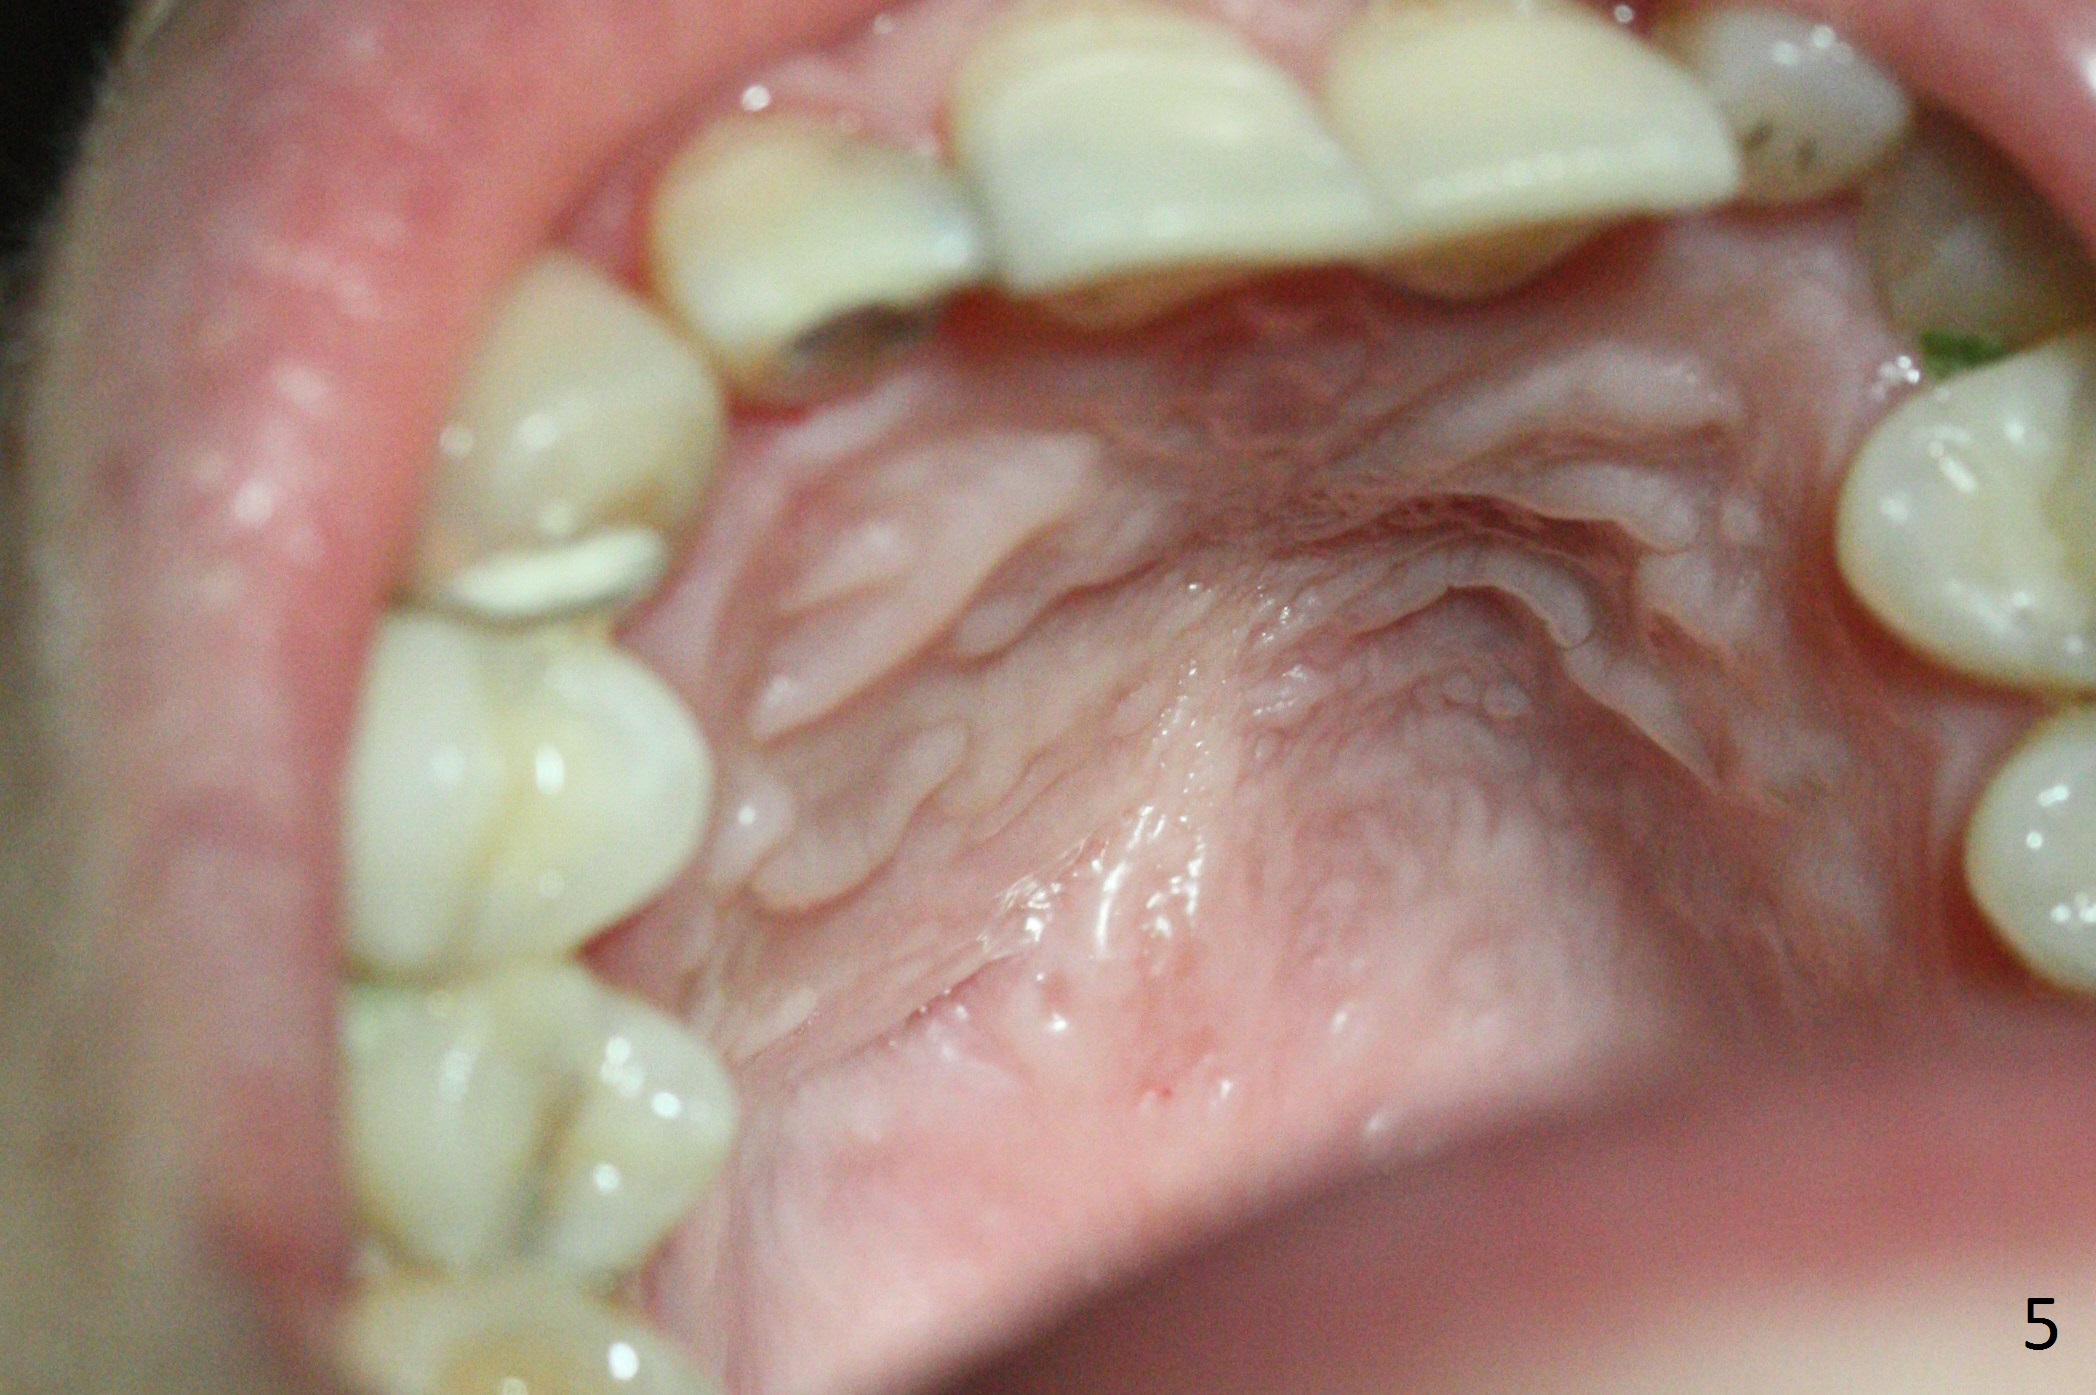

A 30-year-old woman presents to clinic with a large palatal swelling (Fig.1,2). In fact the tooth #7 is necrotic with a periapical radiolucency (Fig.2 arrowheads). RCT is initiated; note the curved canal and file (Fig.3). To reduce the large lesion, Calcium Hydroxide paste is placed in the enlarged canal (Fig.4 *). In a month, the palatal lesion decreases (Fig.5). After re-debridement of the canal, Calcium Hydroxide paste is re-applied.

When this patient returns with improvement of symptoms, RCT will be finished. In fact the swelling relapses a month later (Fig.6). After discussion of possible cyst enucleation and increase in debridement from 30/.04 to 40/.06, a master cone of 40/.06 is inserted (Fig.7) and RCT is finished (Fig.8). Although the patient reports relapse of swelling, the palate looks normal and bone density increases 7 months postop (Fig.9). For 14 implant placement, CT is taken 2 years 1 month post RCT (Fig.10,11). Radiolucency is confined to the apex of the tooth #7 (white *). The labial concavities mesial and distal to the left lateral incisor makes radiolucencies (bone loss) look more radiolucent, creating globumaxillary cyst image. The globumaxillary cyst is a terminology for its shape. It does not mean congenital in nature. The treatment is dependent upon vitality test of the involved teeth.